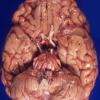

Mucopolysaccharidosis (4)